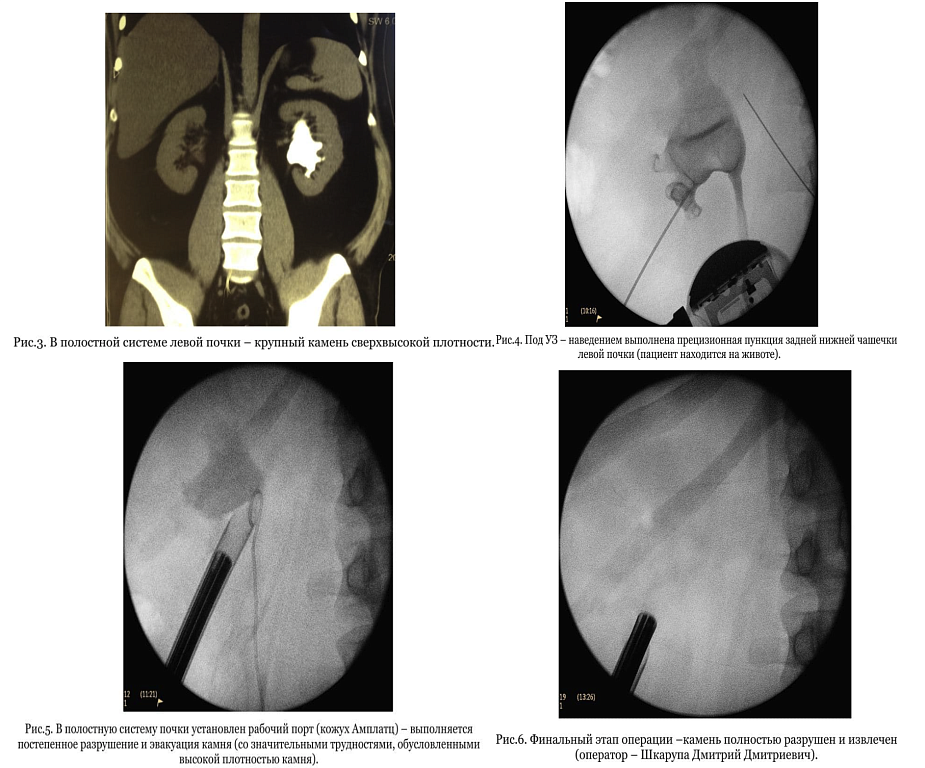

У пациента В. выявлен крупный камень, занимающий все полостную систему левой почки. Сложность клинического случая заключалась в том, что плотность камня превышала 1700 единиц Хаунсфильда (в два раза плотнее кости). Дробление приходилось осуществлять, комбинируя пневматическую и ультразвуковую энергию на максимальной мощности (Рис. 3-6).